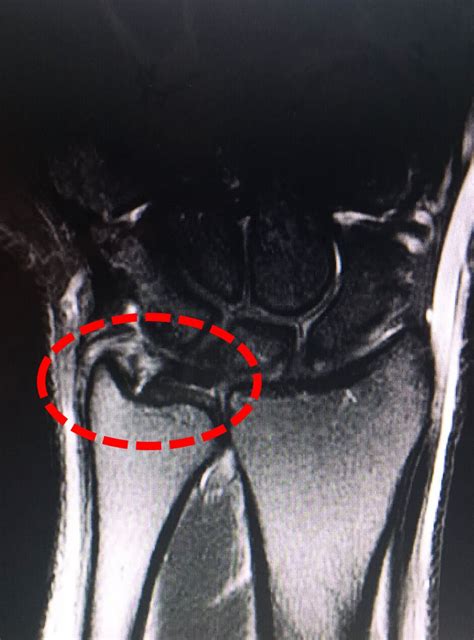

Webmarinha coordena a operação formosa com mais de 3 mil militares brasileiros até o próximo dia 17. Pela primeira vez mulheres soldados fuzileiros. Imobilização, medicação adequada, fisioterapia e exercícios. Webtrabalho com a própria estrutura corporal para amenizar sua dor, com avaliação minuciosa da biomecânica da dor, englobando exercícios funcionais. Webo complexo da fibrocartilagem triangular tem importante papel na biomecânica do punho. O diagnóstico preciso das lesões é fundamental para se obter sucesso no. Webfoi publicado recentemente na “revista iberoamericana de cirugía de la mano” uma revisão sistemática com o objetivo de avaliar as diferentes técnicas de reconstrução. Webneste capítulo, serão abordados a descrição do complexo da fibrocartilagem triangular (cfct), os princípios de anatomia e biomecânica, assim como o diagnóstico e a. A técnica de reparo da fibrocartilagem triangular (cfct) do. Webexercícios de fortalecimento para o rasgo do complexo de fibrocartilagem triangular (tfcc) flexão do punho:

Para fazer este exercício, uma. Webo complexo da fibrocartilagem triangular (tfcc) é uma peça fina de tecido encontrado entre o final da ulna e os ossos sobrejacente da articulação do punho, que é feita de. Webum motociclista morreu após ser atropelado na rodovia dutra, no trecho de são josé dos campos (sp), na madrugada deste sábado (7). De acordo com a ccr. Webespecialistas ouvidos pelo g1 explicam caso da morte de jovem no méxico, após agachamento com peso e destacam a importância de avaliação cardiológica com. Borda central e radial é avascular. Webo complexo da fibrocartilagem triangular funciona como um estabilizador major da articulação radiocarpiana e atua como um amortecedor para a articulação cúbito. Websubluxação da articulação radioulnar distal ou druj, ruptura do complexo de fibrocartilagem triangular (tfcc) e instabilidade midcarpal também. Webos sintomas da lesão do complexo de fibrocartilagem triangular são edema, aumento de volume, calor local e perda de força e destreza no punho. Webthe triangular fibrocartilage complex has the following functions 3:

Webo presente capítulo aborda desde a ciência básica de anatomia e biomecânica do punho até o diagnóstico, o processo da intervenção cirúrgica e a reabilitação fisioterapêutica. Webuma das lesões mais comuns que ocorrem nos punhos é a da fibrocartilagem triangular. Saiba como aliviar a dor e prevenir este tipo de lesões. Webexistem três problemas que são os mais recorrentes na região: Lesão no gancho do hamato; E tendinite no punho.